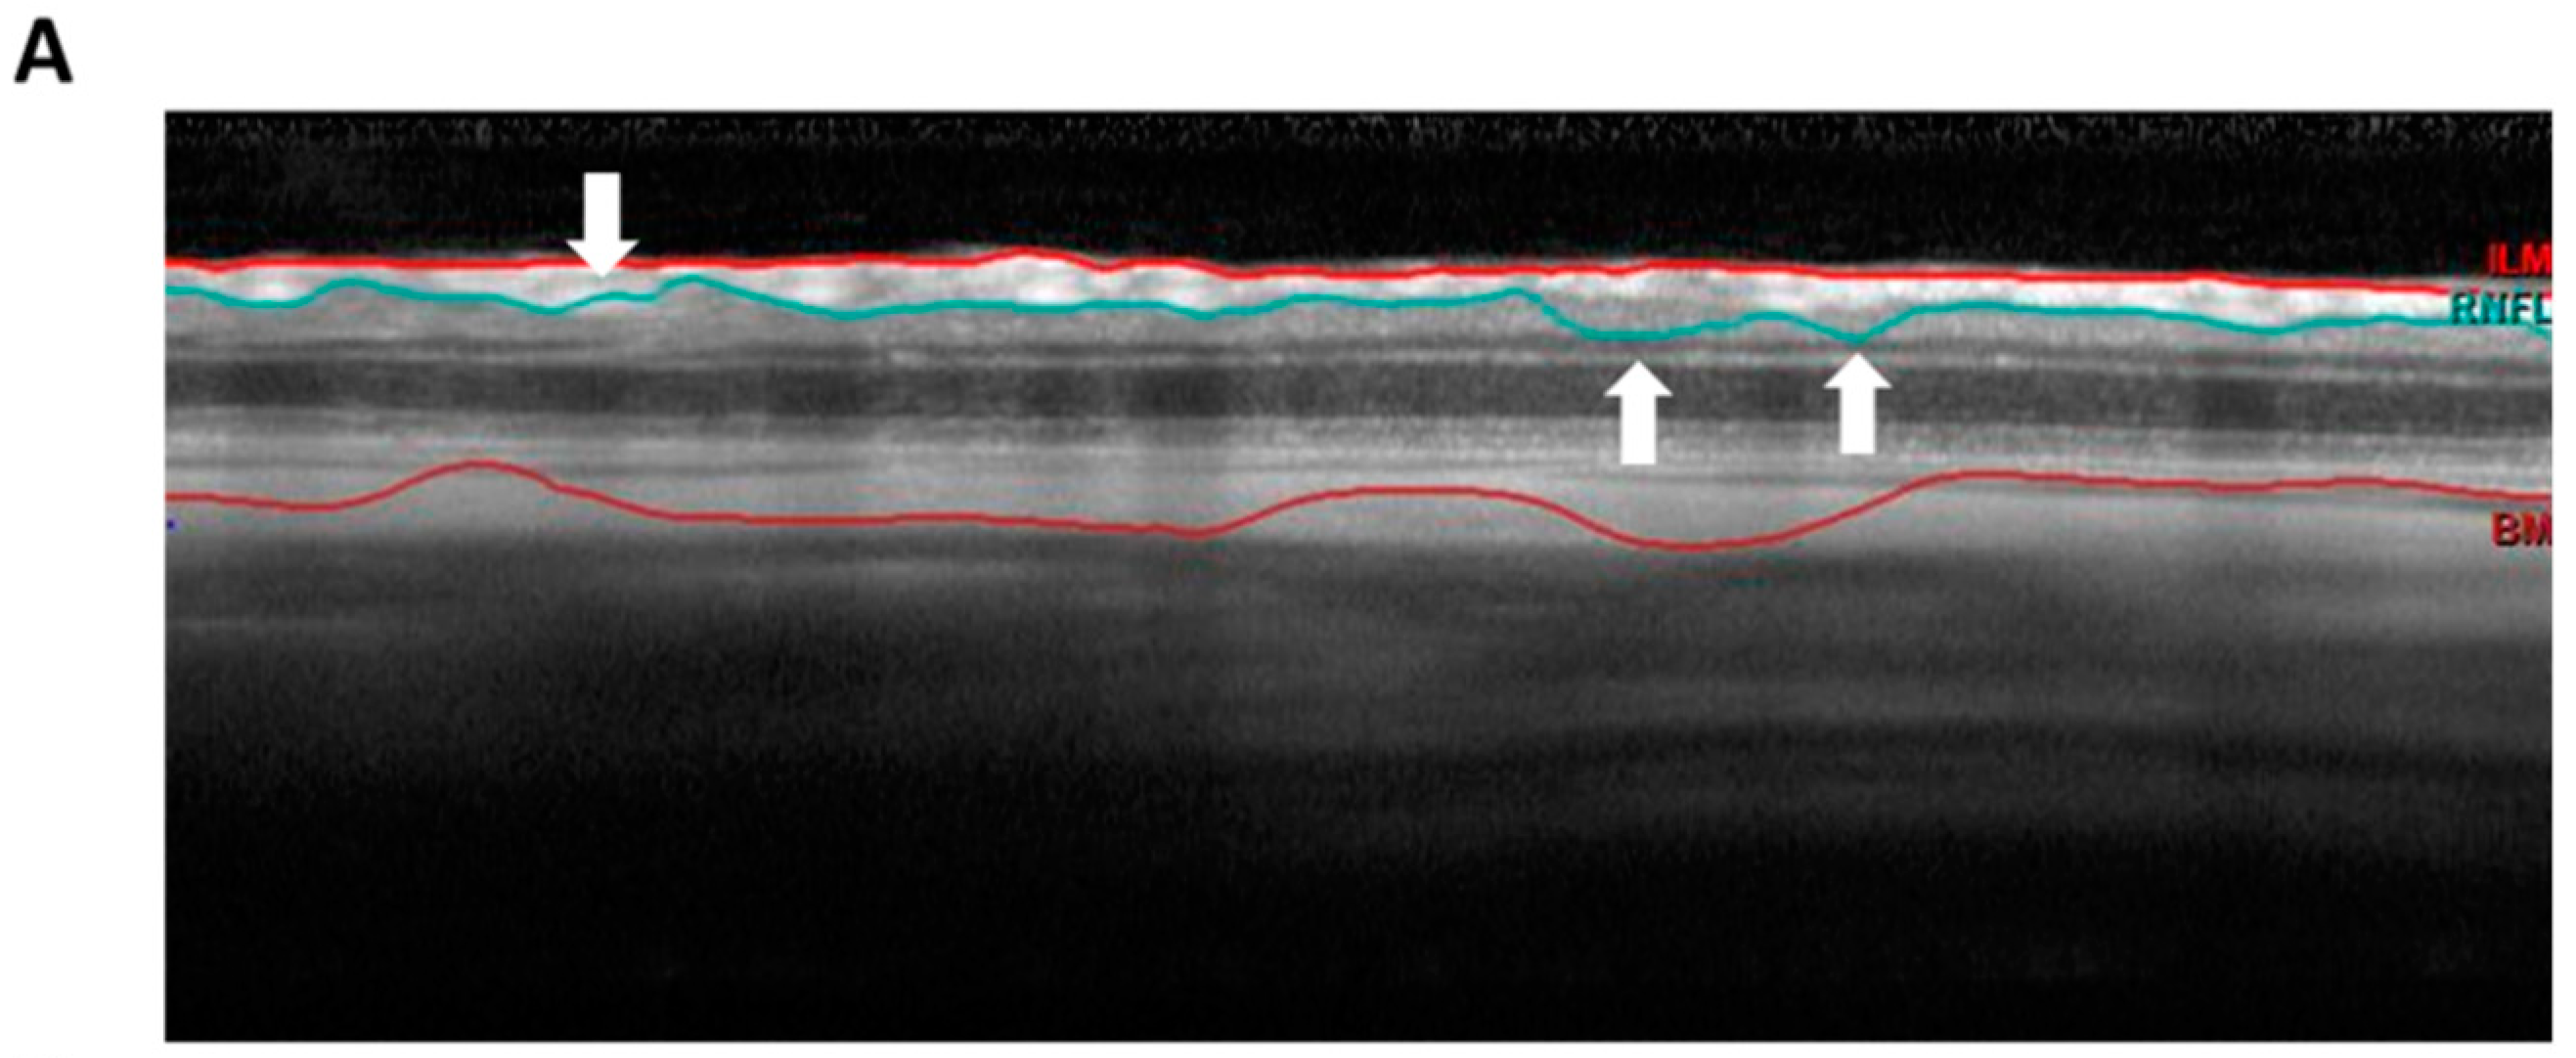

2.3. The Intravitreal Injection of an Anti-DNM1L Ab Reduced the RNFL Thickness Loss